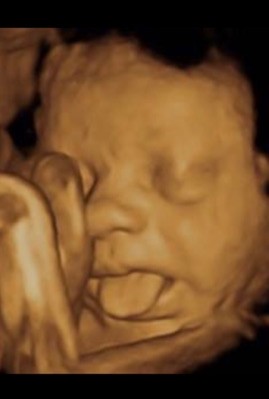

Απεικόνιση 4 διαστάσεων του εμβρύου μέσα στη μήτρα: Δείτε ακόμα και τα χαρακτηριστικά του

Όσο ελκυστική όμως και αν είναι η «φωτογραφική» απεικόνιση του εμβρύου και η τρυφερότητα που κινητοποιεί στους υποψήφιους γονείς, για τους γυναικολόγους είναι ιδιαίτερα σημαντική η λειτουργία της καρδιάς και των αγγείων που «αποκαλύπτονται» στις δυνατότητες του 4d υπερήχου, δίνοντας «όπλα» έγκαιρης διάγνωσης για οποιοδήποτε πρόβλημα προκύψει, έτσι ώστε πλέον να έρχονται στο φως με πληρότητα οι όποιες ανατομικές βλάβες εμφανίζει η ενδομήτρια ζωή του εμβρύου.

«Είναι ευνόητο», καταλήγει ο ιατρός, «ότι για να γίνει εφικτή η άντληση των πλεονεκτημάτων του υπερήχου σε ότι αφορά τον προγεννητικό έλεγχο, απαιτείται εκπαίδευση σε ότι αφορά τις παθολογίες του εμβρύου, δηλαδή πιστοποιημένη εξειδίκευση στην προγεννητική διάγνωση, σε συνδυασμό βέβαια με τη γνώση του 3D-4D υπερήχου».